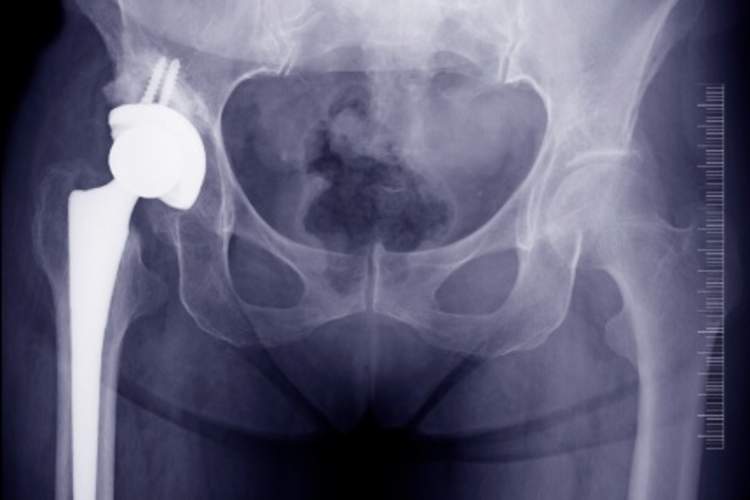

确认和治疗髋部骨折

髋部骨折是骨质疏松症引起的第一类骨折。髋部骨折几乎总是需要手术修复,术后需要数月的物理治疗。